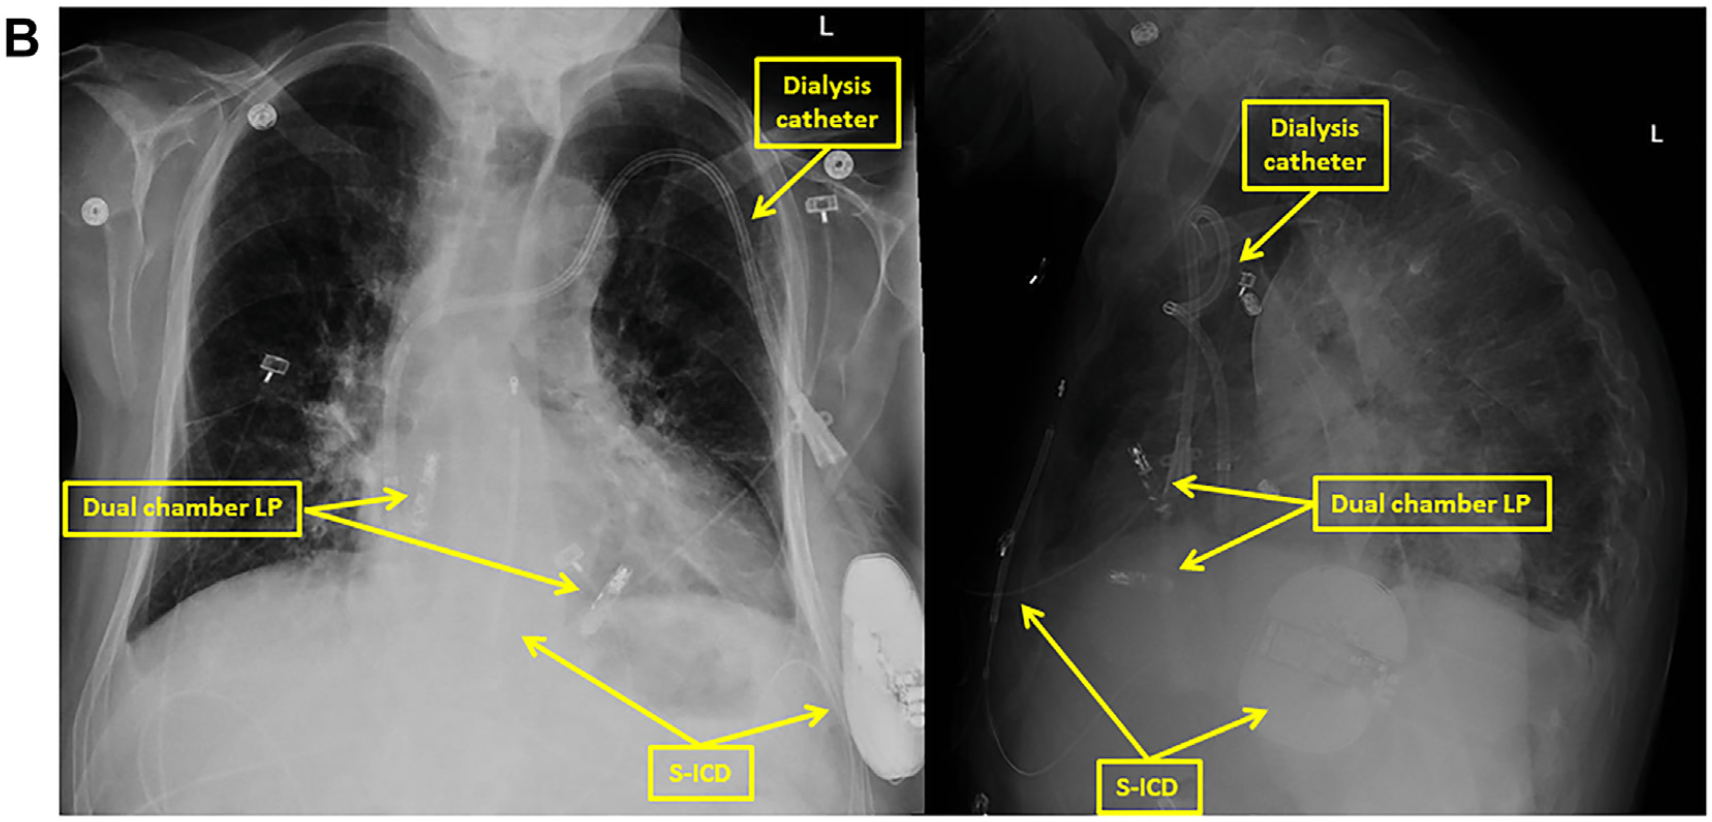

• 但后通过手动筛查工具评估,发现Primary向量和Secondary向量均显示出合理的电图形态,因此,最终将S-ICD植入(图B);

图B 植入后S-ICD与AVEIR DR透视影像图

• 术中,Primary、Secondary向量均显示QRS感知良好,无T波过感知现象;使用Secondary向量成功诱发并终止心室颤动,一次65焦耳电击即成功复律。